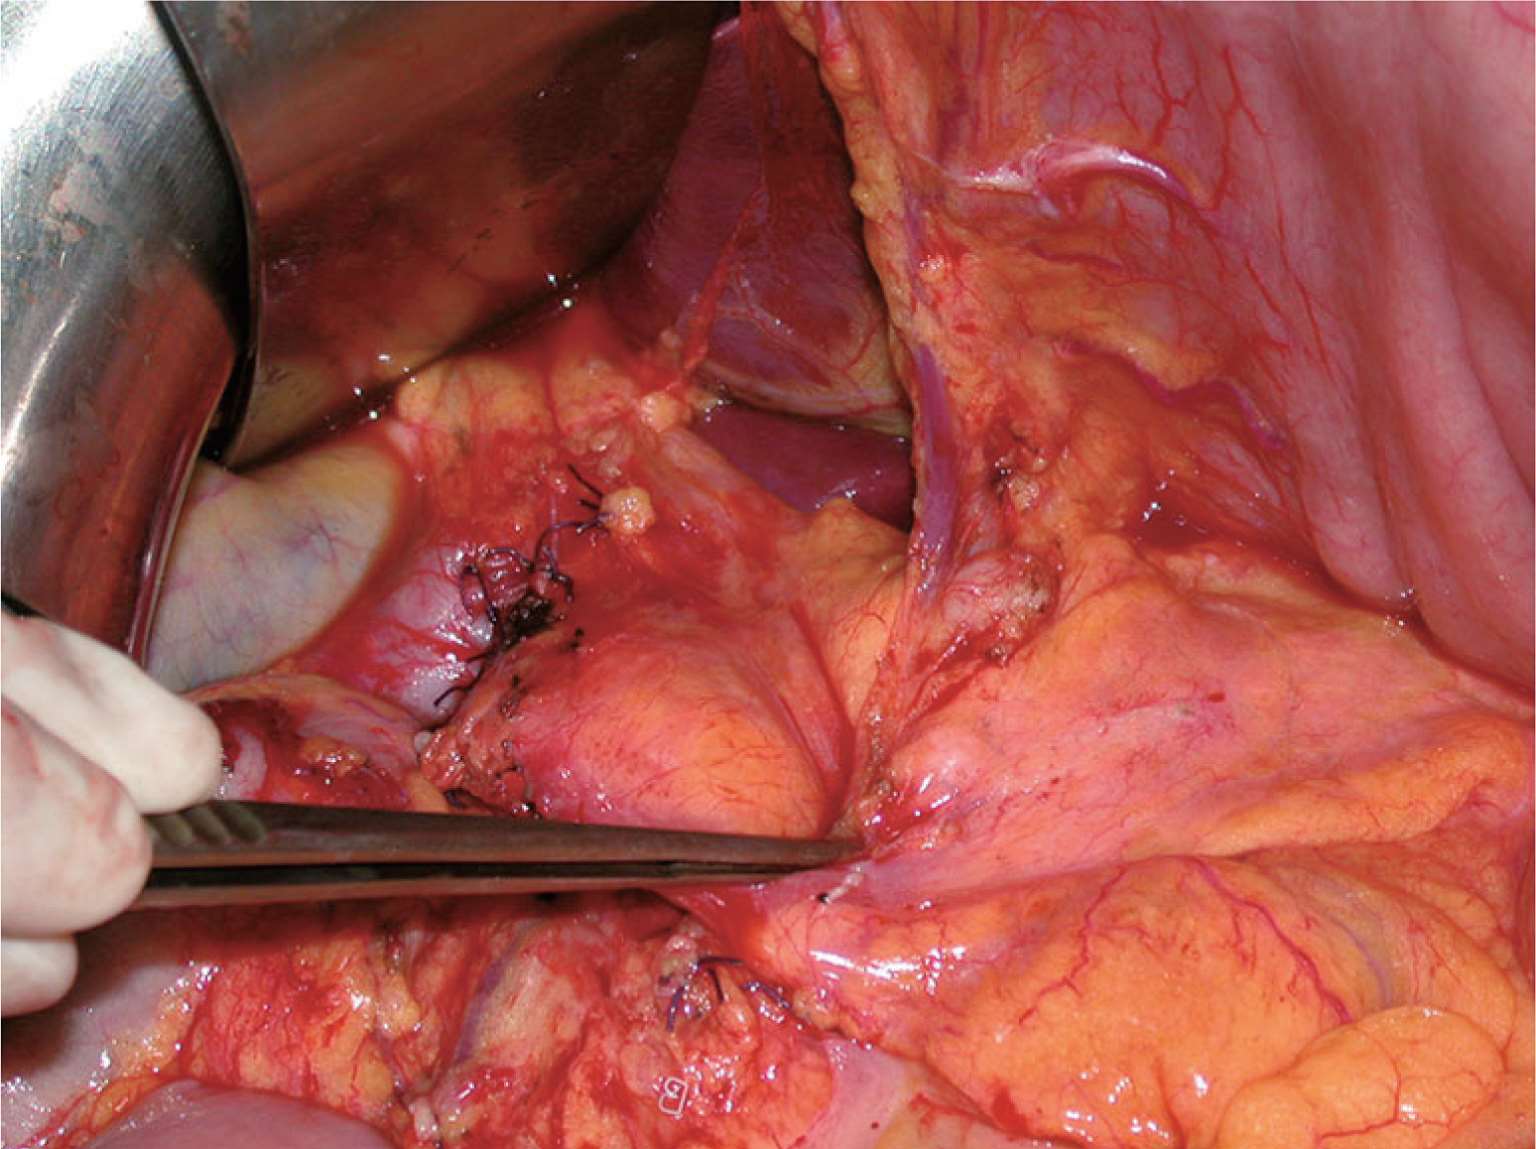

图2-37 变异的肝左动脉(红色箭头)进入肝左叶。